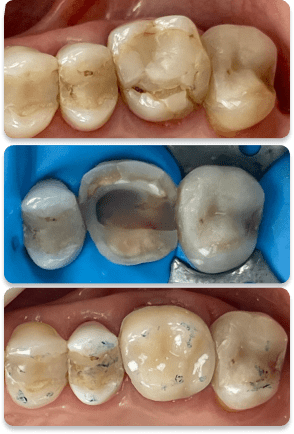

Restauração

Foto 1 – Durante a profilaxia notamos que as duas restaurações estão com infiltrações nas margens e trincas e manchas dentro da resina.

Foto 2.1 – Parece limpo mas não está.

Foto 2.2 – Após jateamento com óxido de alumínio a estrutura do dente está limpa e descontaminada, pronta para receber a restauração

Foto 3 – Restauração pronta com ajuste oclusal e polimento.

Salvando dentes

Foto 1.1 – dente com canal tratado e restauração fraturada.

Foto 1.2 -dente reconstruído e pronto para escaneamento intraoral.

Foto 1.3 – cimentação da onlay. Dente salvo, trabalho finalizado.

Foto 2.1 – remoção total do material antigo e nota-se pouco remanescente dentário.

Foto 2.2 – dente limpo com jateamento de óxido de alumínio.

Foto 2.3 – reconstrução em resina para melhor adaptação da onlay em porcelana .